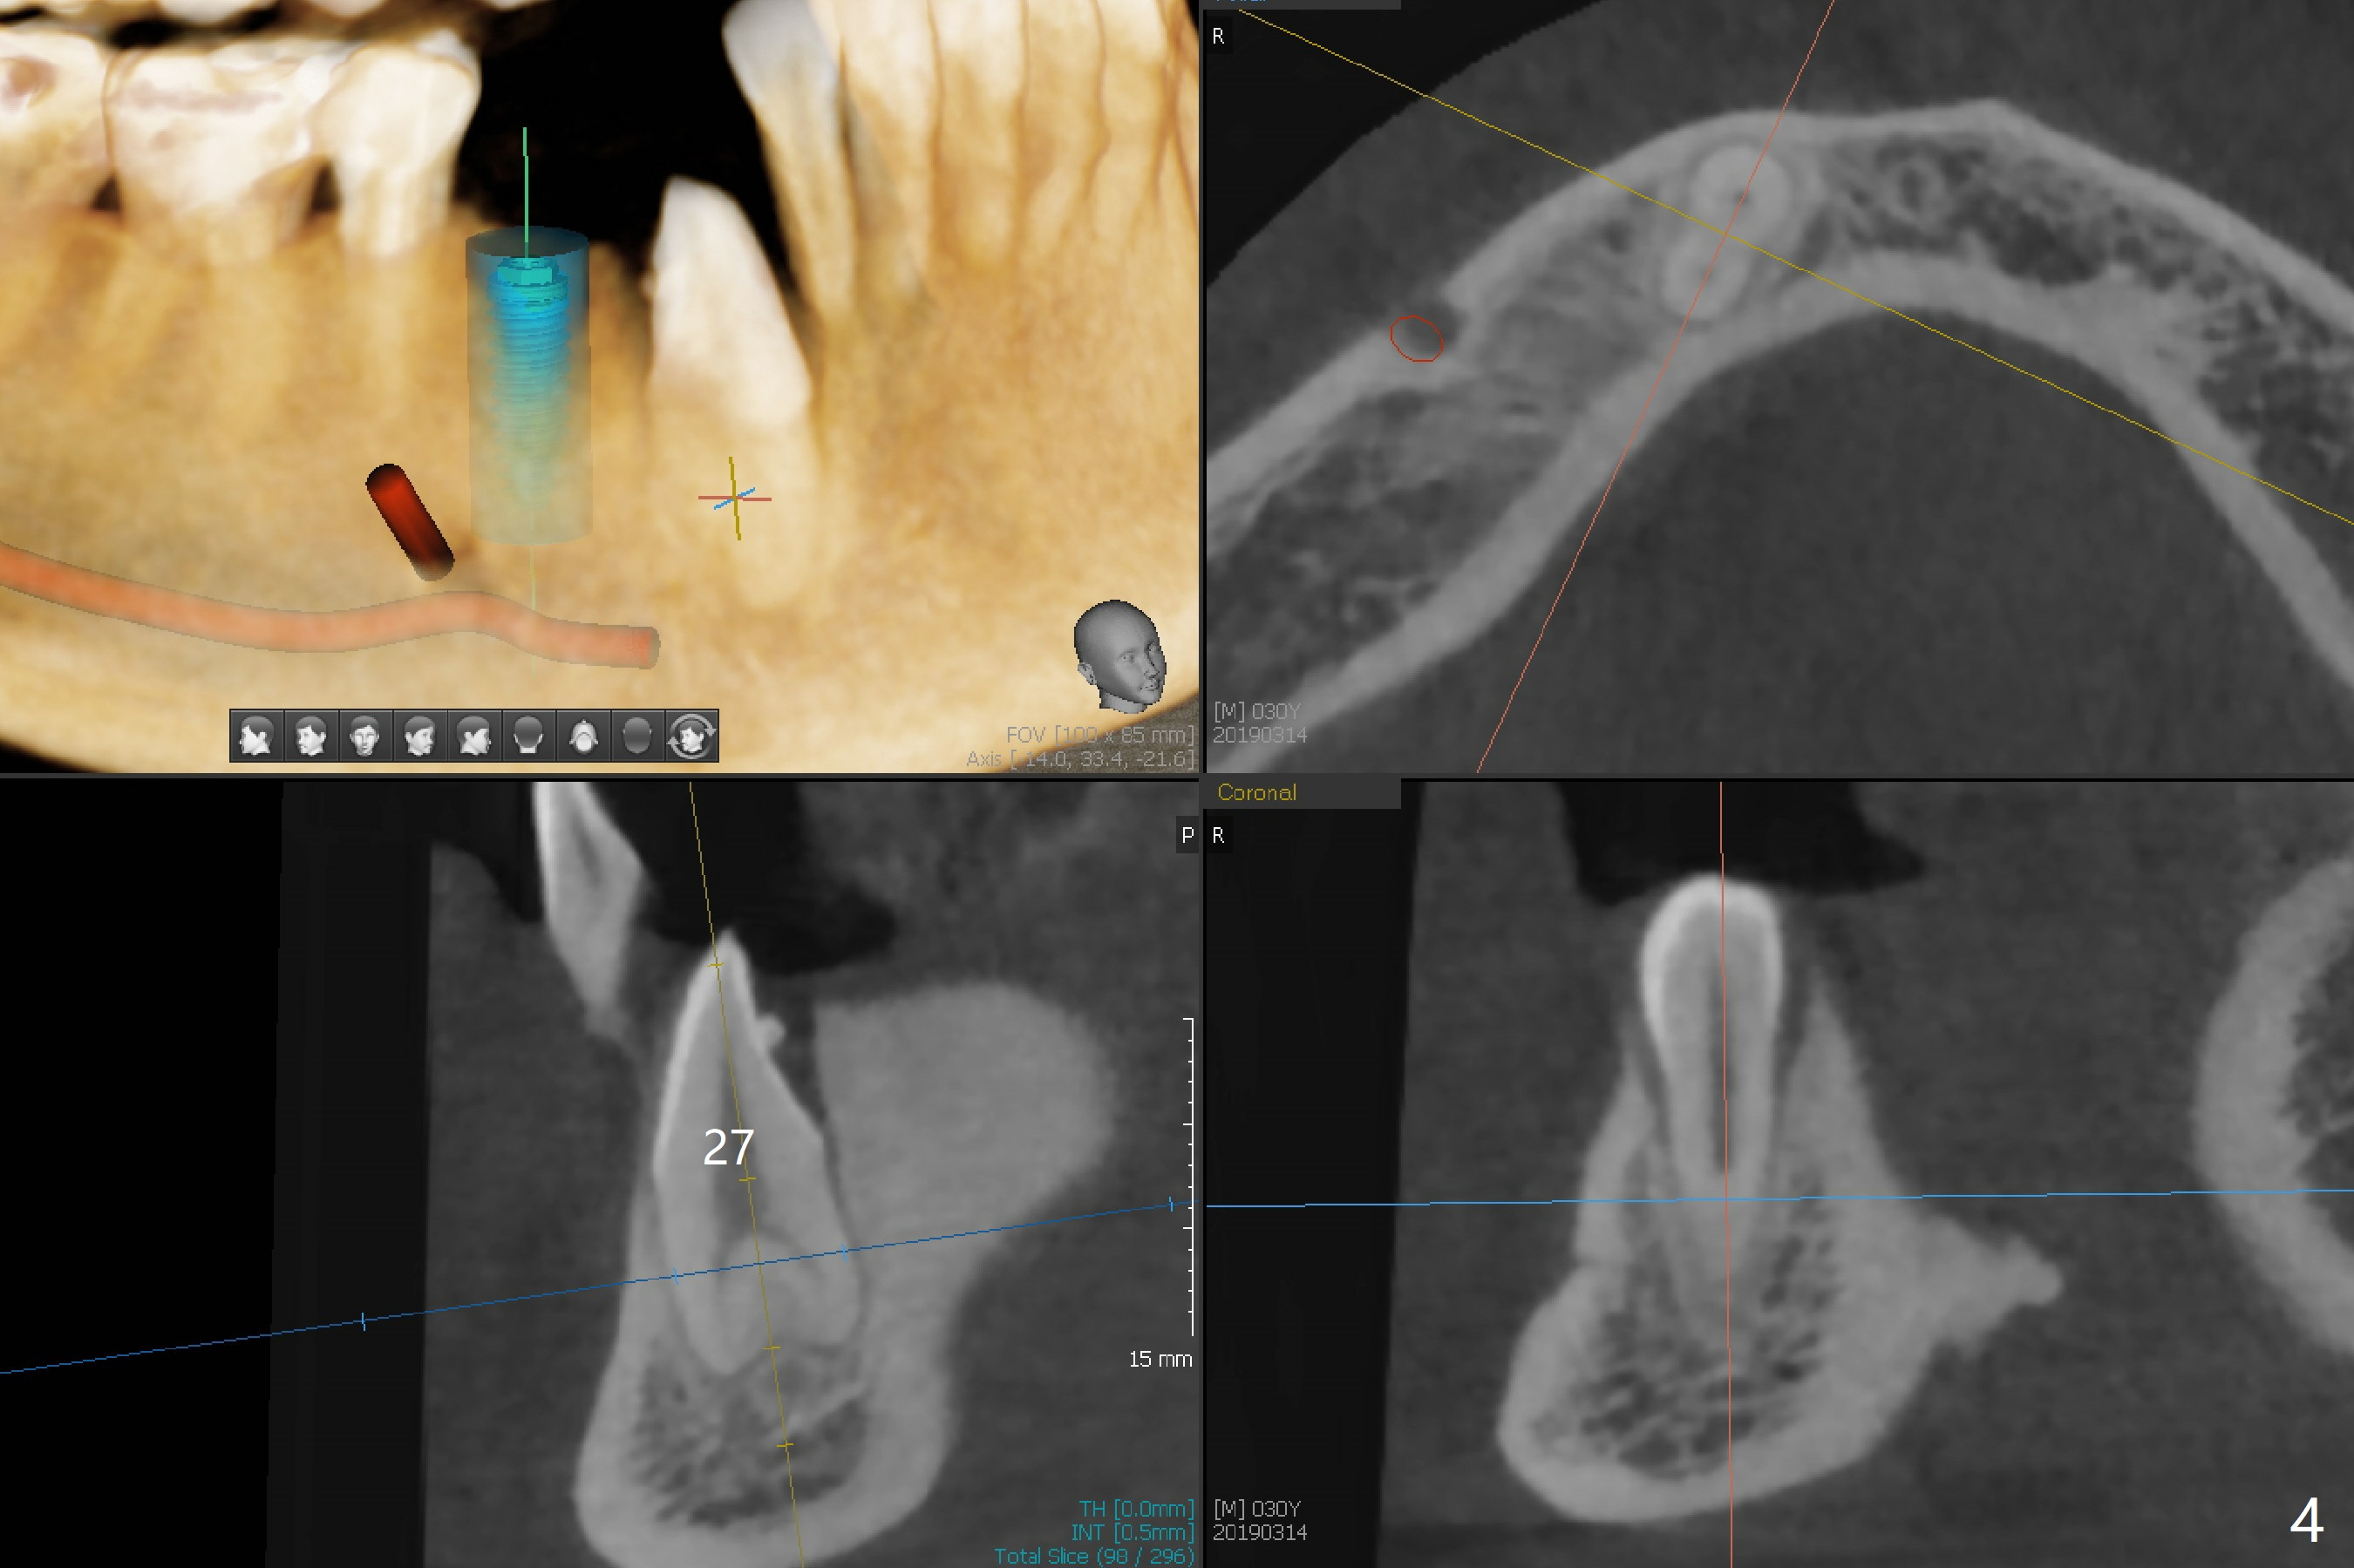

A 30-year-old man requests orthodontic extrusion of the impacted lower right canine and implant at the next site (Fig.1). Since the canine rotates with wider mesiodistal width of the crown (Fig.2 red line), the implant should be smaller and placed distal (Fig.2 red arrow). The extrusion will gain the bone to the distal surface of the lateral incisor (Fig.2, 3*). In fact the tooth #27 is malformed in that the root is split (Fig.4, as compared to the tooth #22 (Fig.5)). Surgical guide will be used for precision.